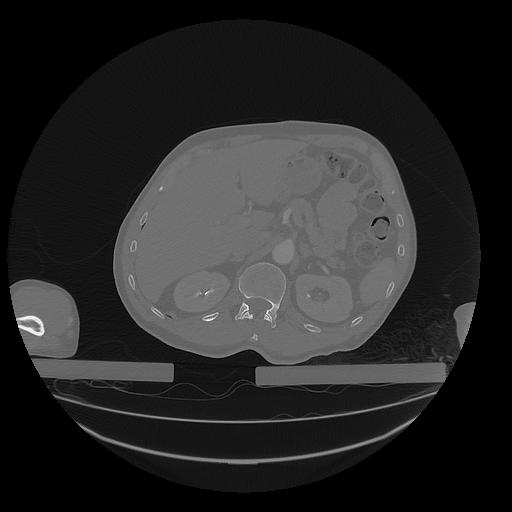

31 PULMON,CE,Vol,1.0,PULMON,,